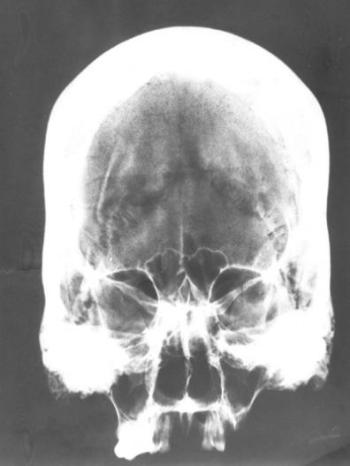

A Morgagni-Stewart-Morel betegség (szinonimák: Morgagni szindróma, hyperostosis frontalis interna, craniopathia hyperostotica) a 40 év feletti nők, hypophysis dysfunctiójának következménye. Tünetei közül a virilizáció, magas vérnyomás, fejfájás, elhízás és diabetes mellitus, paleopathologiai anyagon nem ismerhetők fel. A koponyacsontok (elsősorban a homlokcsont) megvastagszanak, elérhetik a 30–35 mm-t (szemben a normális 5–7 mm-rel), belfelületük egyenetlen, dudoros. A kórkép egyéb jelei, a súlyos csontritkulás, ízületi bántalmak stb. nem specifikusak. A régészeti irodalomban számos esetismertetés szerepel (Hahn és Charnetzki 1980, Gladykowska-Rzeczycka 1987 stb.). A koponyák rtgvizsgálatával két alkalommal találtunk extrém vastag (22 mm feletti) boltozatot (133. ábra). A calvaria csontjainak hyperostosisa a torzítottakon gyakori, ám az elkülönítő kórisme egyszerű.

133. ábra. Extrém vastagságú (20 mm), hyperostoticus boltozati csontok Morgagni-Stewart-Morel szindrómás 40–60 éves nő koponyáján. 10–12. század